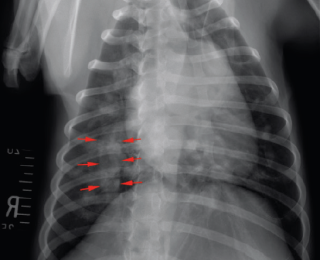

Thoracic radiographs revealed enlargement of the pulmonary arteries, mild to moderate right ventricular enlargement and a moderate diffuse, unstructured interstitial pattern with patchy alveolar areas within the right cranial and middle lung lobes (see Figures 1 and 2). Echocardiography revealed right atrial enlargement with bulging of the interatrial septum to the left, mild subjective enlargement of the right ventricle and mild to moderate central pulmonic regurgitation with a mildly elevated velocity (2.8m/s; reference value <2.2m/s). The pulmonary artery was mildly enlarged and contained multiple mobile, tortuous linear hyperechoic structures, likely to reflect the presence of adult worms (see Figure 3). The laboratory test results in combination with the imaging findings were consistent with a diagnosis of canine dirofilariasis.